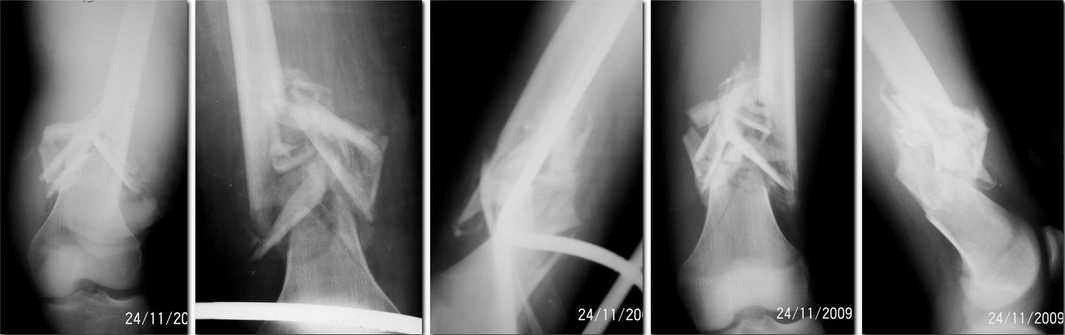

Уважаемые коллеги! Пациент 17-ти лет, был сбит электричкой 10.10.09. Основную проблему

составил открытый мелкооскольчатый перелом н/3 правой бедренной кости. Мелкие сочетанные

повреждения - СГМ, мелкие раны, вывих плеча... По наружной поверхности правого бедра в

проекции перелома определялась обширная рана неправильной формы до 20см с разможжением

мягких тканей. Рана была ушита, дренирована, заживала вторично с умеренным нагноением,

находился на скелетном вытяжении. Долго мальчика пылались перевести в МОДОХБ, затем в

ведомственную больницу по месту работы родителей... и когда все от него отказались - он

достался мне. В настоящее время подвижности в зоне перелома уже нет, но наружной поверхности

правого бедра грубый Г-образный рубец с небольшими участками грануляций. Снимки говорят

сами. Планируем БИОС ретроградно с открытой репозицией. Господа, поделитесь опытом. Не

стоит ли дополнить покрытием штифта цементом с антибиотиком? Уровень проведения

дистальных блокирующих винтов с учетом сохраняющейся зоны роста? Использование

дистрактора?